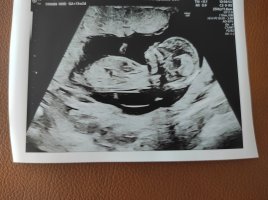

Osaako joku arvioida meidän kuvasta? Kätilö sanoi, että tuo ympyröity olisi napanupra, eikä siitä voi päätellä mitään. Facebookin nub-teoria ryhmässä sanottin, että se olisi nub?!

Rv 12+3.